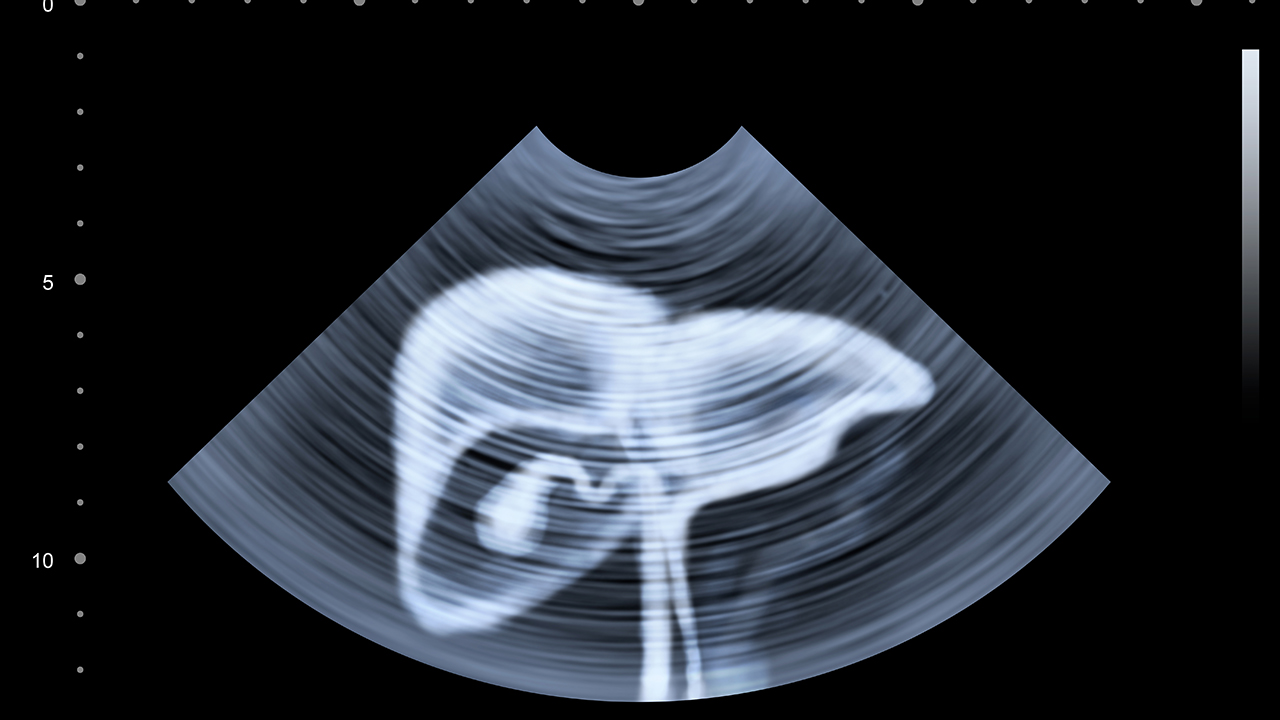

肝癌預防需重視乙肝疫苗接種和定期肝臟超聲檢查,尤其慢性肝病患者應每6個(gè)月進(jìn)行AFP檢測和影像學(xué)監測。日常生活中需嚴格戒酒,避免霉變食物攝入,保持規律作息。對于已確診患者,建議建立營(yíng)養支持計劃,適量補充支鏈氨基酸,術(shù)后定期復查增強CT或MRI。